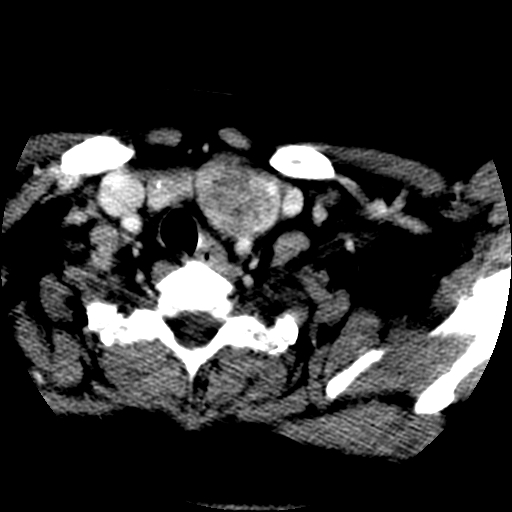

标题: CT25491:女,55岁,发现左侧甲状腺肿块一个月。 [打印本页]

女,55岁,发现左侧甲状腺肿块一个月,彩超示:甲状腺多发结节伴左叶结节液化。

左右叶都有,峡部也受累,有钙化,考虑结甲可能性大。

腺瘤囊变

考虑左侧甲状腺腺瘤囊变。